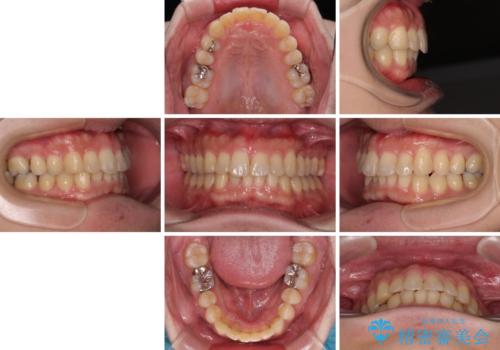

深い咬み合わせで顎が疲れる ワイヤー矯正でディープバイトを解消

- 1年4ヶ月

下顎が左側にずれているため、上下正中は最大限合わせられるところまで合わせるゴールとなりました。